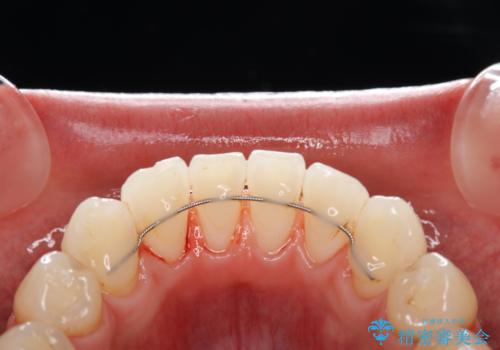

- コーヒーを毎日飲むため、歯が黒くなり気になるとのことでした。

また、以前他院にて矯正治療を行い、前歯の裏側には保定装置がついていることで磨きにくいため機械的に細かい部分のクリーニングも希望とのことでした。

エアフローワンは、特殊なパウダーを混ぜた水を水面にジェット噴射することでバイオフィルム(プラーク)・ステイン(着色)・早期歯石を天然歯やインプラント周囲から除去することが可能な歯面清掃器具です。

従来の荒い研磨剤などを用いた歯面への負担が大きいクリーニングとは異なり、歯質の負担を最小限にした歯面清掃と歯周ポケット内のメンテナンスを行えます。